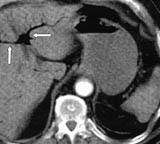

Ved ankomst i sykehuset var han kaldsvettende, forvirret og klaget over smerter i venstre bein. Han hadde ikke buksmerter. Han hadde puls 190/min, uregelmessig, systolisk blodtrykk 210 mm Hg og normal kroppstemperatur. Buken var lett utspilt, uten ømhet eller andre tegn på peritonitt. Venstre bein hadde nedsatt sirkulasjon. EKG viste raskt atrieflimmer. Pasienten var kritisk syk. Behandling av hans raske atrieflimmer med verapamil og metoprolol bedret ikke situasjonen. Blodprøver viste Hb 19,0 g/100 ml (jf. 17,4 g/100 ml to måneder tidligere), leukocytter 21,7 × 10 9 /l, trombocytter 226 × 10 9 /l, CRP 138 mg/l, natrium 141 mmol/l, kalium 3,3 mmol/l, albumin 42,3 g/l, kreatinin 140 µ mol/l, bilirubin 25 µ mol/l, ASAT 262 U/l, ALAT 139 U/l, CK 227 U/l, amylase 139 U/l. CT abdomen viste en normalt kalibrert aorta med tromber i venstre a. iliaca og i a. mesenterica superior. Det forelå en fyllingsdefekt nær avgangen av truncus coeliacus, samt fravær av kontrastfylling i coeliacusgebetet. Forgrening av luft var synlig i leveren (fig 1), helt ut til leverkapselen (fig 2). Luft var også synlig i den ekstrahepatiske del av portvenen, samt i miltvenen og i mesenteriale vener (fig 3). Det forelå ingen utvidelse av magesekken, og heller ingen intramural luft. Vi mistenkte en vaskulær katastrofe i buken. På vei til operasjonsstuen mistet pasienten bevisstheten og døde.